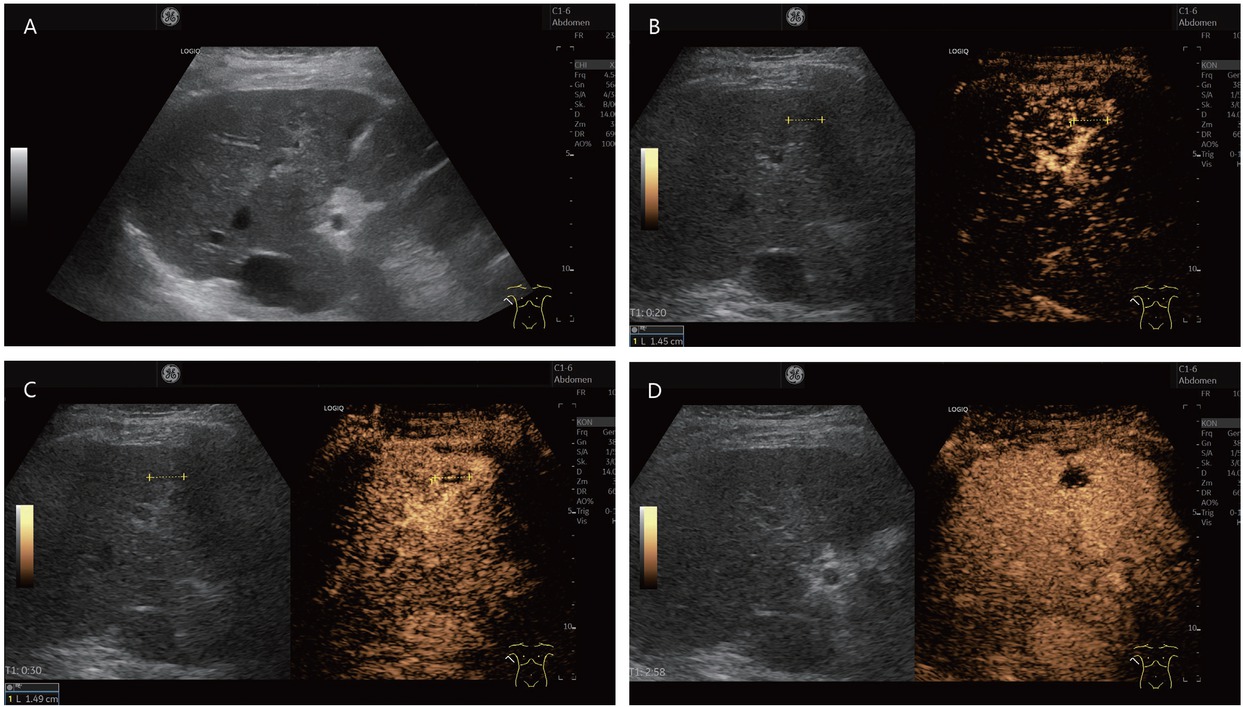

A typical feature of hemangiomas in CEUS is a smooth contrast-receiving ring in the arterial phase with a peripheral, discontinuous nodular (syn.: globular) enhancement with progressive centripetal contrast (Figure 1). The fill-in in the late phase can be complete or incomplete. (Partially) thrombosed hemangiomas do not fill up completely (Figure 2).[9,19]

An 80-year-old female presented with thrombosed hemangioma (in between markers) and liver cirrhosis after hepatitis C infection. She had normal AFP and no previous known tumor disease. Hypoechoic inhomogeneous liver lesion with echogenic rim on B-mode ultrasonography (A). No enhancement in the arterial phase, only suggested rim (B). At the beginning of the portal venous phase, the lesion is not enhanced, except for a few vascular pixels. These are seen in the marginal area and cannot be clearly assigned for differential diagnosis (C). In the late CEUS phase, the lesion remains completely avascular. A retraction of the liver contour is seen above the lesion. On MRI, the lesion was assigned as a thrombosed hemangioma. Thrombosed hemangioma with capsular retraction is a finding that has been described on MRI for hemangiomas in liver cirrhosis. Capsular retraction can also be seen in tumors (D). CEUS: contrast-enhanced ultrasonography; MRI: magnetic resonance imaging; AFP: alpha-fetoprotein.